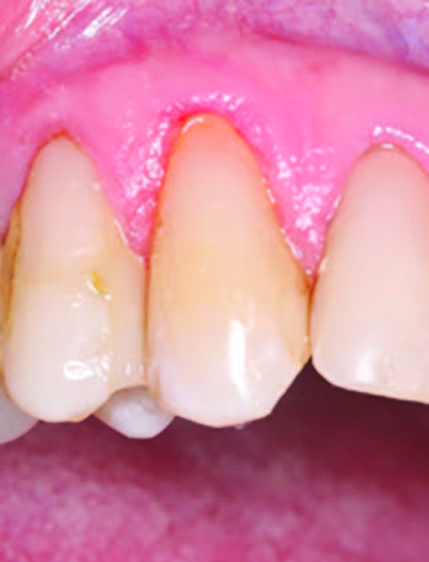

Figure 2. Placement of the retraction cord to improve isolation and access to the cervical area prior to preparation.